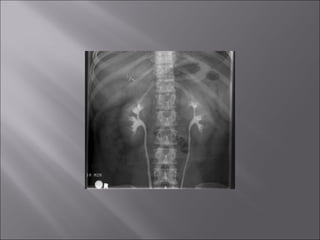

 Torso, vertebral, cranial, shoulder, hipradiograph: as if the patient is standing in an upright position.

 Decubitus chest and abdominal radiographs:so that the side of the patient that was positioned upward when radiograph was taken is upward on the hung radiograph.